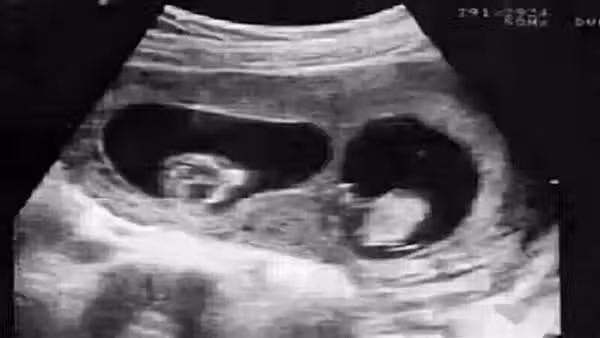

千辛萬苦生下娃,驗DNA卻是親叔叔的!爸爸是獨生子,哪兒來的叔叔?

第二種則是,孕期裡媽媽和胎寶寶的血液循環雖然是分開的,但部分母體細胞還是能通過胎盤進入到寶寶身體裡的,自然而然寶寶也可能帶上媽媽的一部分DNA。事實上根據研究發現,有8到9成的準媽媽都有這種現象。並且像是生二胎的時候,媽媽體內攜帶的大寶的基因,就可能進入到二胎的體內。這種也被稱為微嵌合體現象。